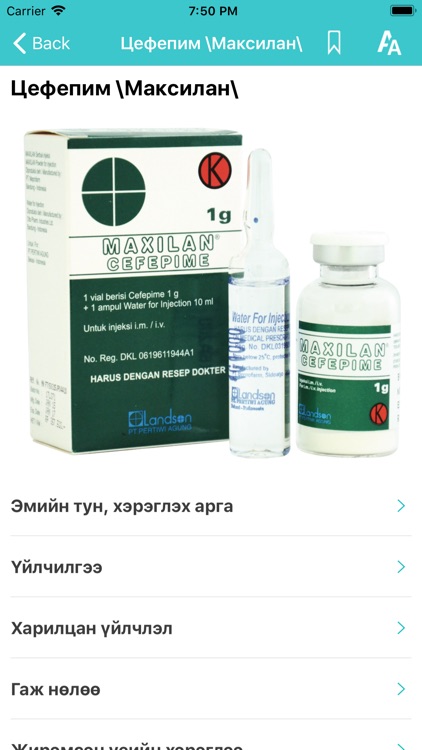

Эрүүл мэндийн лавлах аппликейшн

Эрүүл мэндийн лавлах аппликейшн.

Эрүүл мэндийн лавлах аппликейшн.